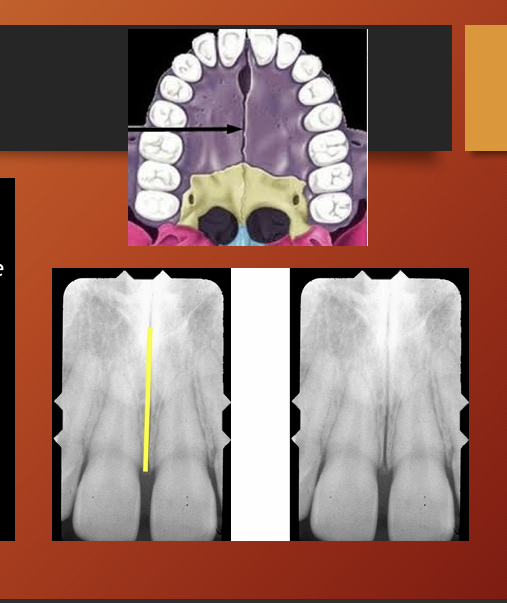

intermaxillary suture

incisive foramen

intermaxillary suture aka the median suture

in a panoramic it appears as a thin radiolucent (black) line in the midline between the two portions of maxilla